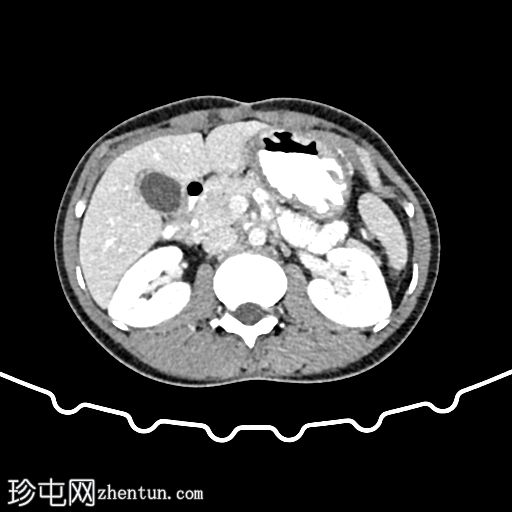

CT

轴位

肝外胆管、肝内胆管及胆囊内可见气体。后续增强(静脉)检查中加用口服造影剂,结果显示造影剂从十二指肠反流至胆总管,最终进入胆囊。